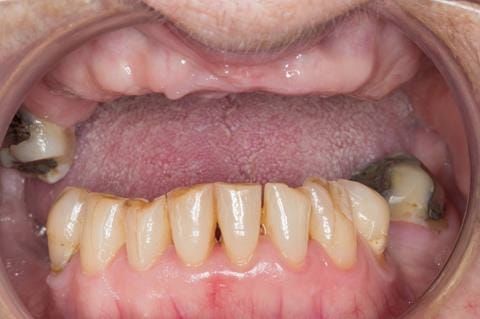

- Eight mandibular anterior teeth worn incisal edges from now extracted maxillary anterior crowns. Gingivitis - owing to inadequate oral hygiene.

Following consultation and second discussion appointment the patient chose to have option 2 namely, a window denture - maxillary cobalt chromium based partial denture. The clinical situation and treatment process is shown in detail below with photographs. The patient was successfully rehabilitated with this and her quality of life considerably improved. The clinical work was provided by Finlay and the technical work by Rowan.